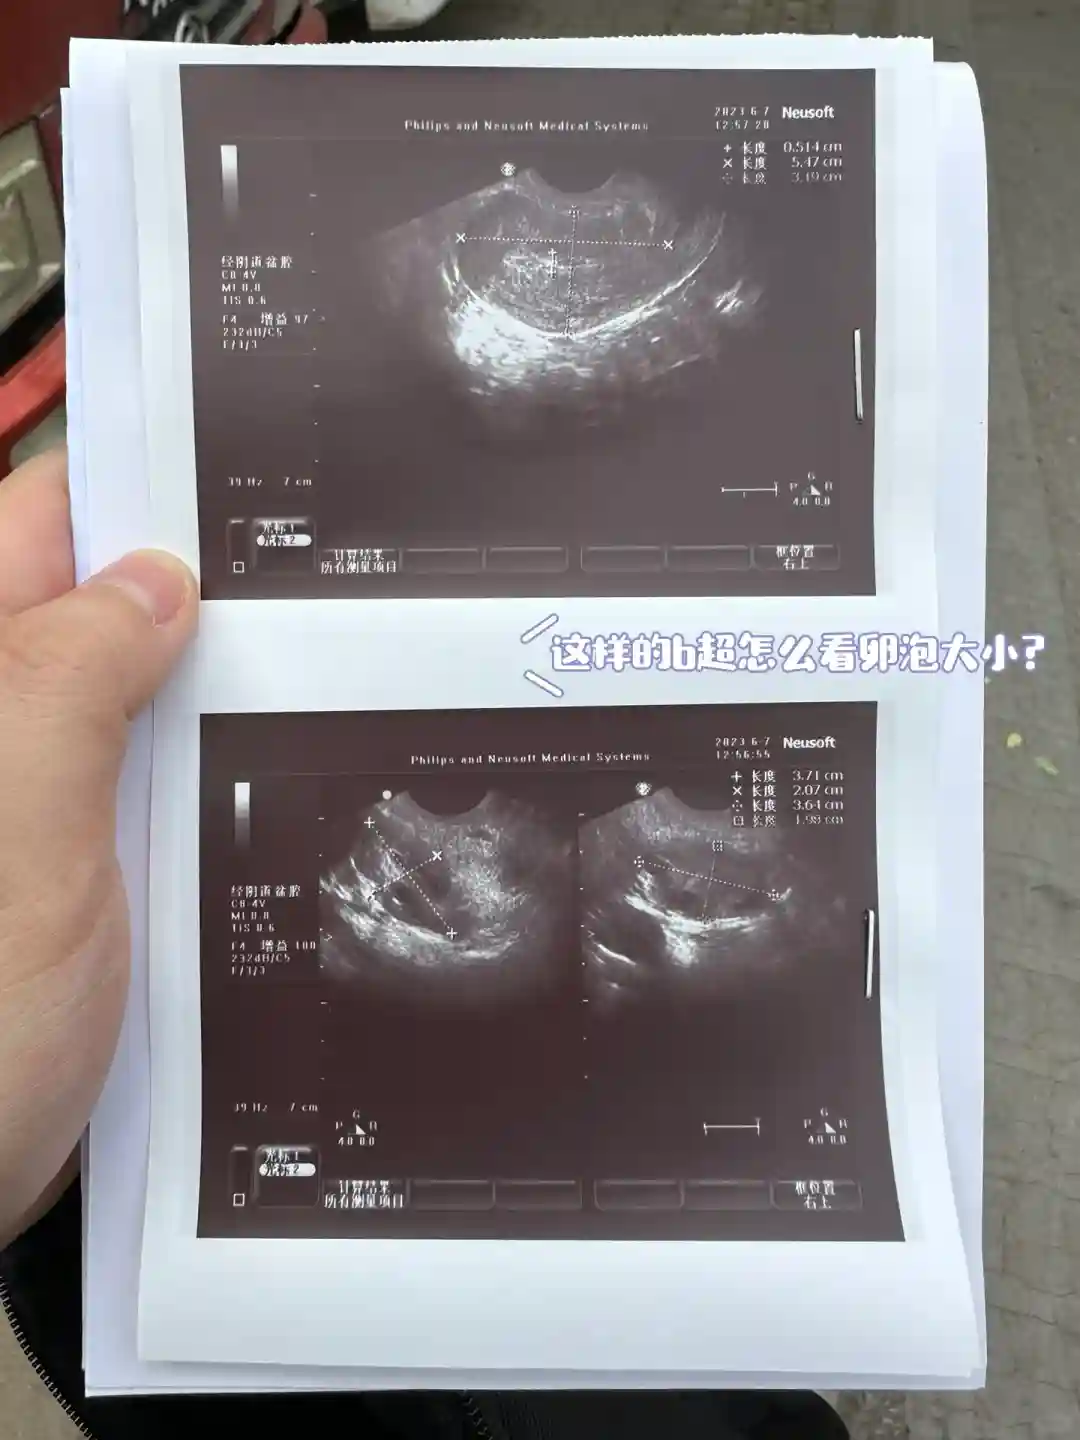

麒麟丸 一次6g 一天3次6.14号返院监测情况…妇婴的b超单看不懂,谁能帮我看看这小b超单子怎么看?我的卵泡是多大